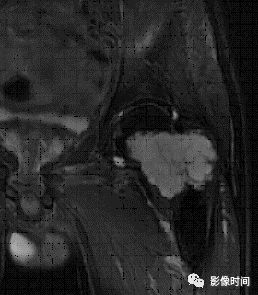

(二)瘤软骨  为肿瘤细胞产生的软骨基质,多来源于软骨类肿瘤,或内有化生瘤软骨成分的其他肿瘤如成软骨型骨肉瘤。瘤软骨为软组织密度,未钙化时,主要通过 MRI 检查显示。

由于瘤软骨多由富含水分及粘多糖的透明软骨构成,故 T1WI 呈偏低信号,T2WI 或 PDWI 呈明显高信号,被低信号的纤维间隔分开呈分叶状(图 24、图 25a-b),增强扫描多呈不均匀分隔状强化(图 25c),主要是纤维间隔强化,瘤软骨强化不明显之故。

图 24  瘤软骨:内生软骨瘤

图 25  瘤软骨:内生软骨瘤